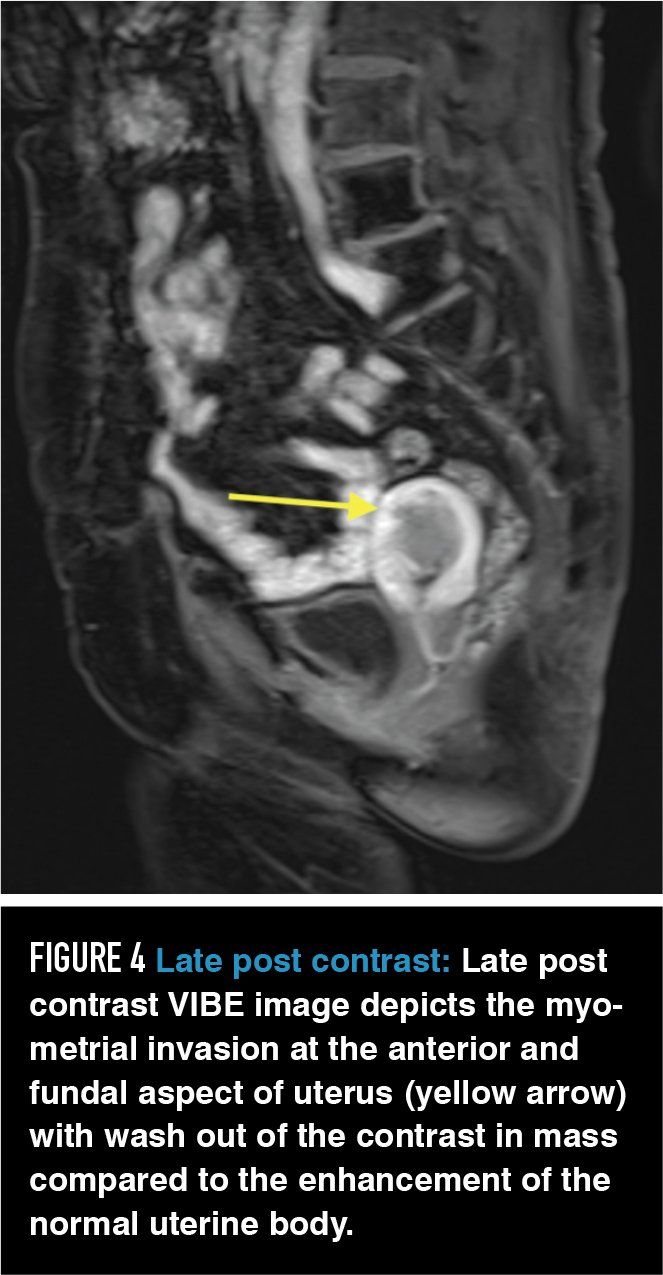

Figure 4

The incremental additional clinical information that is gained with use of GBCA in MRI evaluation of variant pelvic anatomy and suspected benign pathology is small. Adding GBCA has been shown to improve evaluation of myometrial invasion from endometrial carcinoma13 and identification of the correct primary tumor when there are multiple sites of biopsy-proven uterine adenocarcinoma.14 Contrast may also be useful in identifying vulvar cancers and occult inguinal metastases15 and it has shown to be useful in identifying neoplastic nodules within complex adnexal lesions and distinguishing endometriosis from pelvic inflammatory disease.16,17